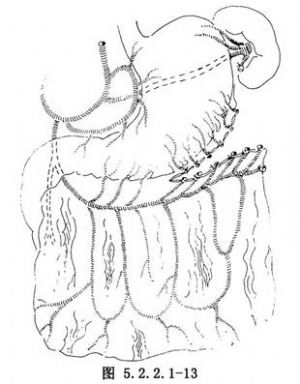

(3)大網膜遊離轉移至胸壁:於腹部取正中或旁正中切口,切斷胃網膜左動脈,以胃網膜右動脈爲供血血管製成帶蒂網膜瓣(圖5.2.2.1-13)。經皮下隧道上提至胸部創口內。爲上提網膜所製作的隧道要寬闊,以免壓迫阻礙網膜動、靜脈的血流。縫合腹膜及腹壁切口。然後用3-0滌綸線將網膜瓣覆蓋縫合在Marlex網上。